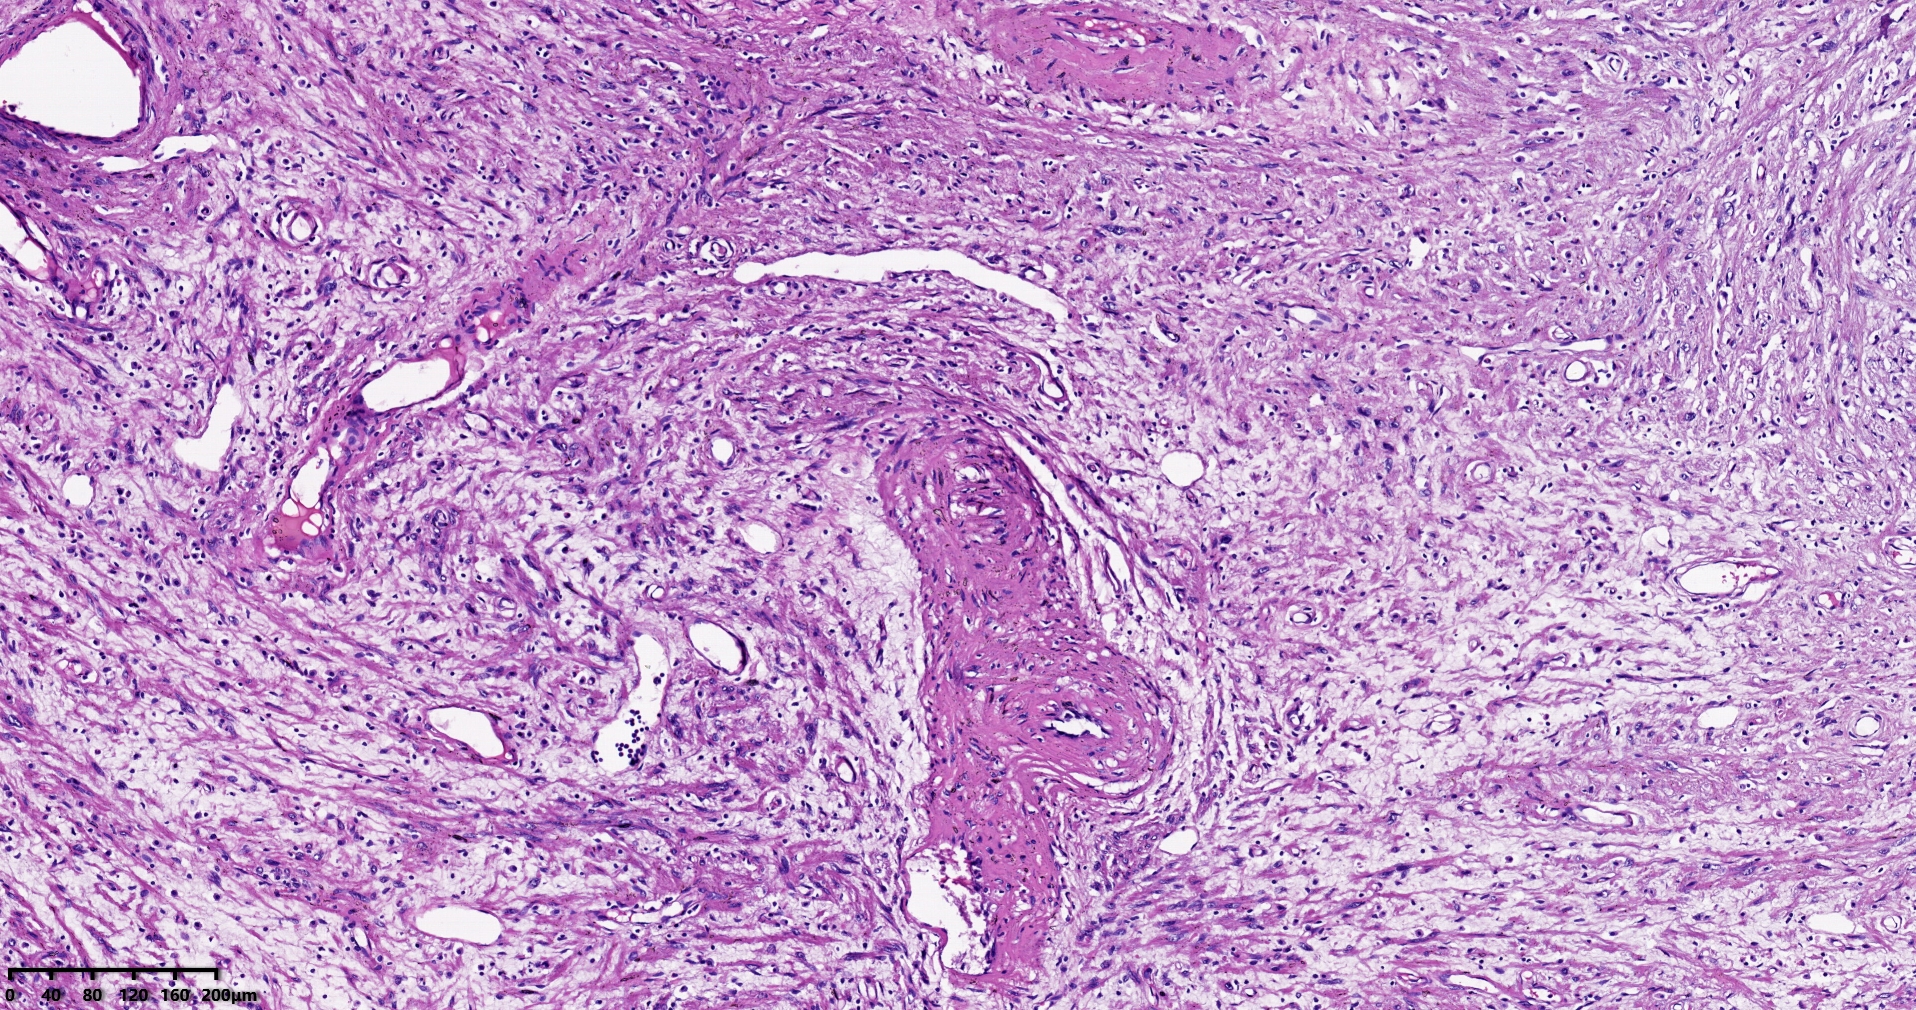

结肠肝曲息肉状肿物,平滑肌瘤?胃肠道间质瘤?炎性纤维性息肉?

性别

男

年龄

56岁

临床诊断

结肠肝曲息肉

一般病史

不详

标本名称

大体所见

灰红色椭圆形息肉一个,直径2.5cm,蒂长0.5cm,切面灰白灰红色,质中。

请路过的老师指教。

考虑间质瘤?

就HE形态而言,间质瘤的可能性要大一些,建议做免疫组化协助鉴别。